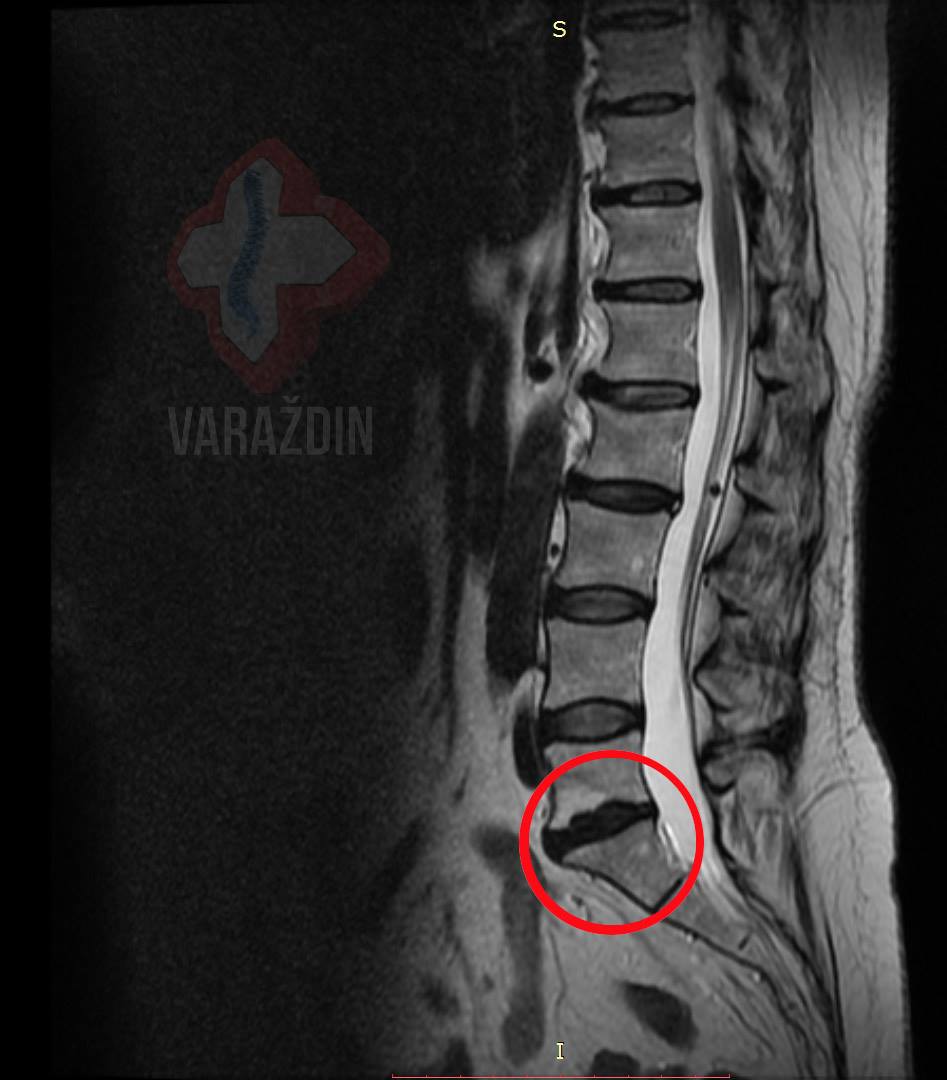

Klijent ima 28 godina. U Nado centar Varaždin došao na

preporuku liječnika – napravljeno 10 tretmana. Osim problema sa

sjedenjem i hodanjem, prisutna je bol u leđima sa širenjem trnaca

u nogu. Nakon obavljenih 10 tretmana kod kontrolne MR nema više

nikakve boli. Prije DTK (dekompresijskog tretmana kralježnice)

obavljala se fizikalna terapija koja nije davala značajne pomake,

odn. samo je problem ublažila privremeno. Nakon 10 tretmana već

godinu dana nema nikakvih bolova upravo radi saniranja samog

uzroka problema – discus herniju u segmentu L5 – S1 radi kojeg su

se problemi i pojavili.